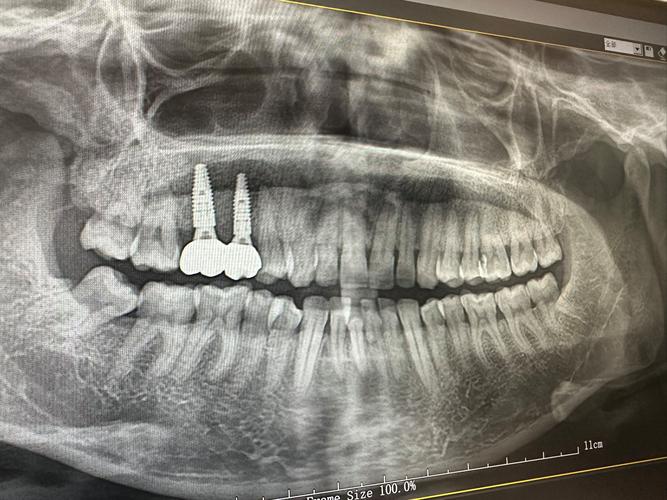

术前评估是手术成功的基础,需通过CBCT(锥形束CT)三维重建测量缺牙区骨高度、宽度、密度,明确骨缺损范围;同时评估患者全身状况,排除糖尿病未控制、严重骨质疏松、凝血功能障碍等禁忌症,对于自体骨移植,还需供骨区(如髂骨)的评估,确保骨量充足且取骨后并发症风险低。

术后愈合阶段是骨再生关键,植骨材料需与受植区骨组织通过“爬行替代”或“直接愈合”实现骨整合,自体骨愈合周期约3-6个月,异体骨或人工骨可能需6-9个月,期间需避免植骨区受力,定期复查CBCT评估骨形成情况,待骨密度和骨量达标后,再进行二期种植体植入手术。